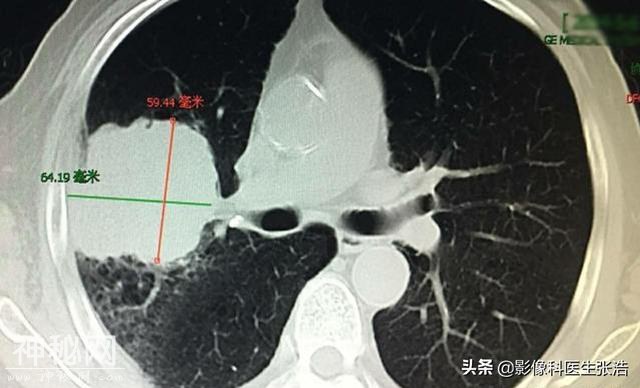

上图是右肺巨大肺癌肿块,侵犯到右侧胸壁结构。